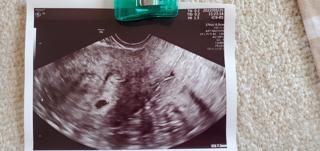

写真:5w0d:ぽんさん

初めての診察で無事胎嚢が確認できました。

自分の体がちゃんと赤ちゃんを迎える準備をしていて不思議でした。

2週間後に心拍確認の診察です。